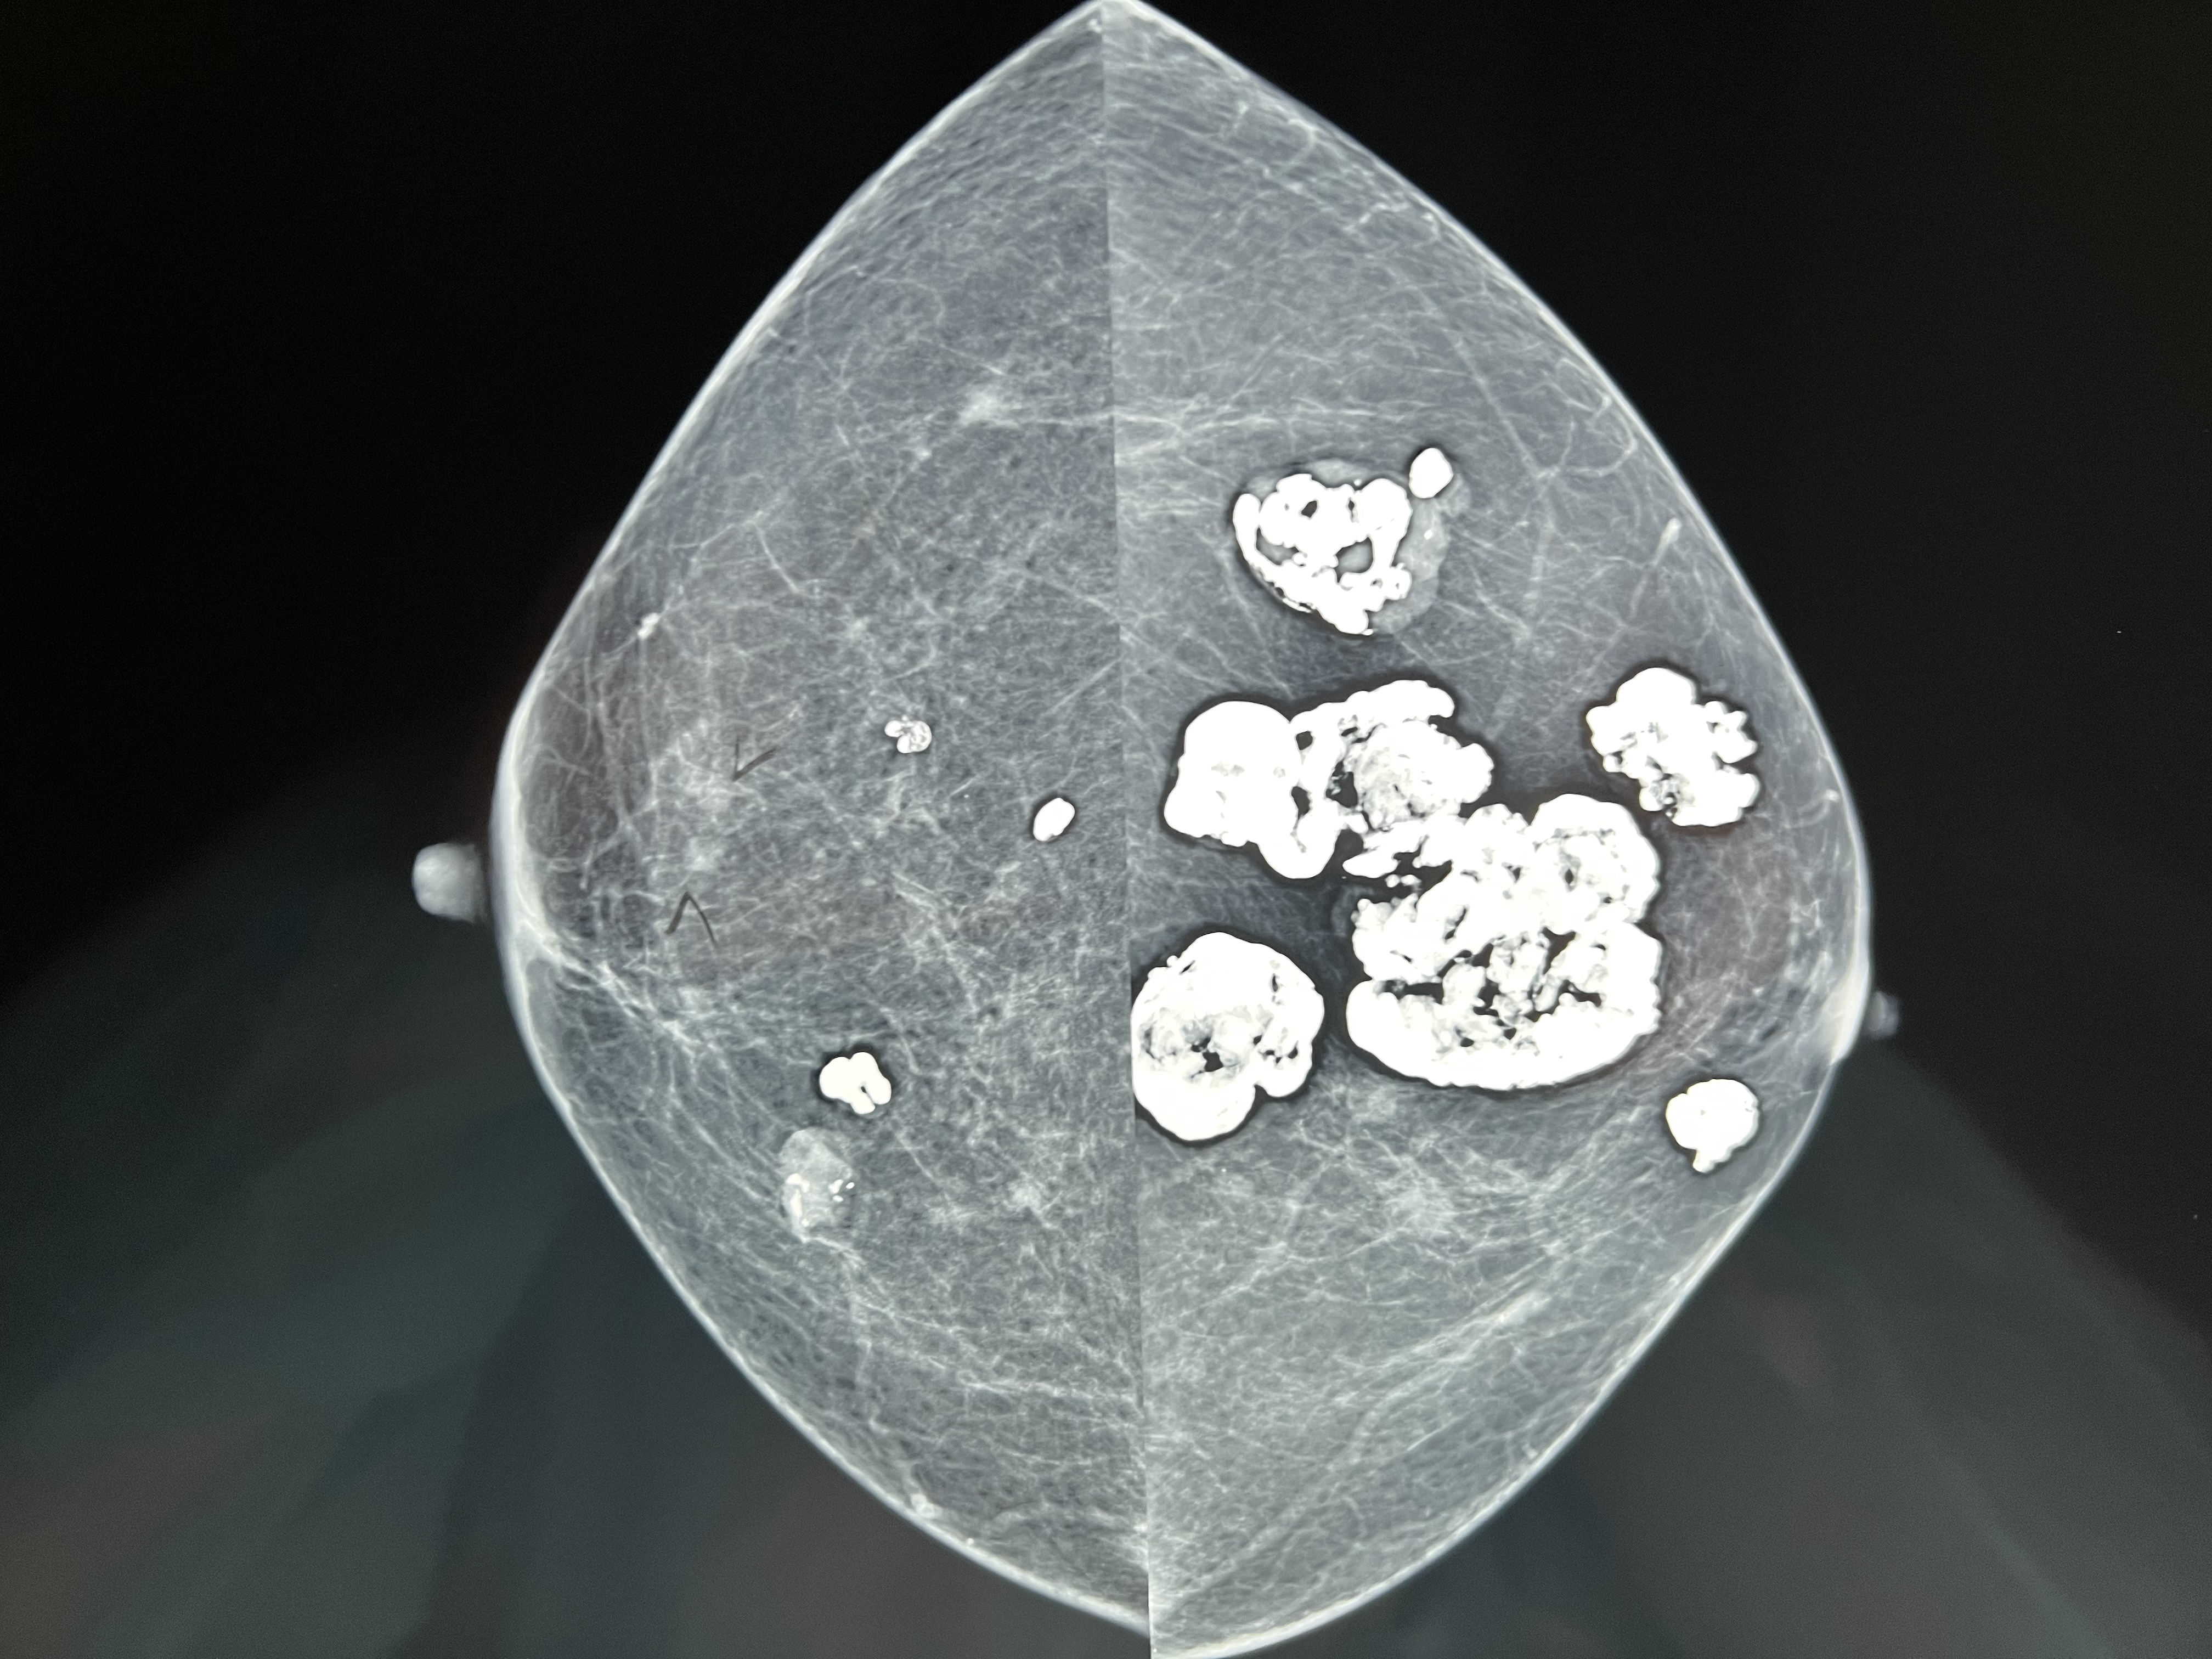

A Sociedade Americana de Radiologia recomenda que as mulheres transgênero façam mamografias da mesma forma que as mulheres cisgênero. No entanto, a mamografia pode ser mais difícil de interpretar devido a implantes mamários ou preenchimentos

Homens transgênero que fizeram mastectomia não precisam de mamografia, mas devem fazer exames clínicos anuais das mamas. Os que ainda mantém suas mamas devem fazer o rastreio a partir dos 50 anos.